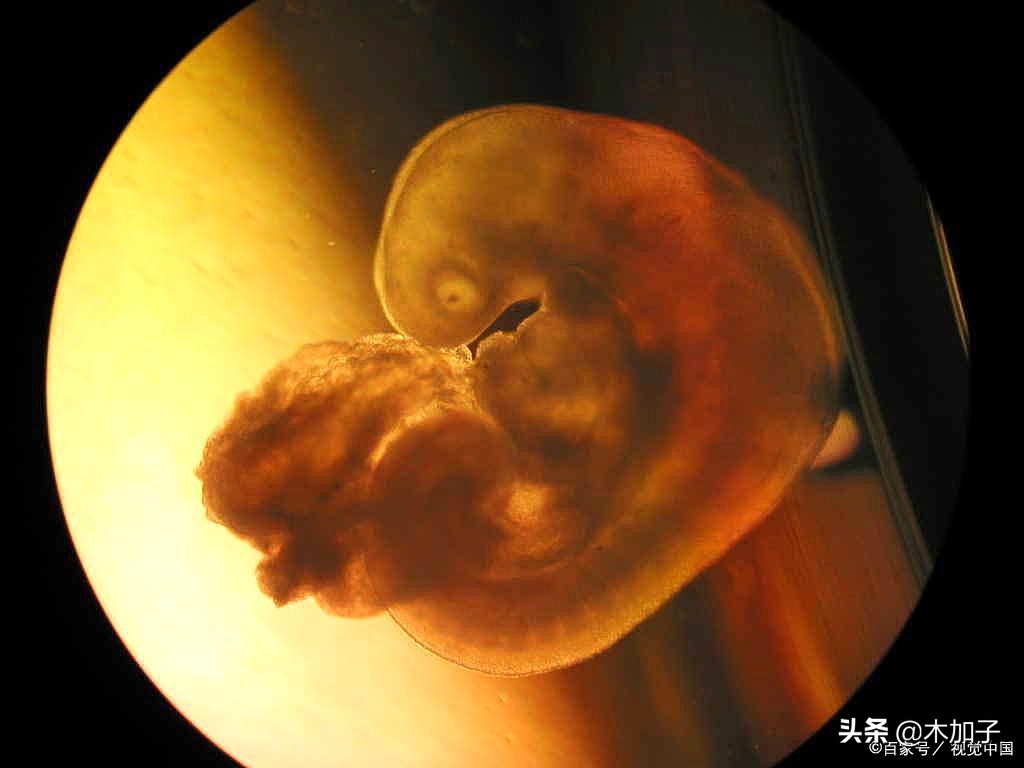

我,最倒霉的那个,没有享过片刻的喜悦,第一次怀孕,刚检查就告诉我是宫外孕,经过了一周的折磨,复查有了孕囊,但告诉我还没有胎芽,又提心吊胆的在孕吐中度过,一周瘦了十斤,好不容易孕吐停了,医生又说空囊,没有发育,于是流着泪进了手术室。

第二次怀孕,刚开始挺好的,hcg、孕酮都挺高的,只是检查的时间早了,只有孕囊,后来两个月的时候再去复查,医生就说已经胎停了,因为胎芽大小显示六周,孕囊显示八周,而且孕酮也下降了,无奈有做了手术。